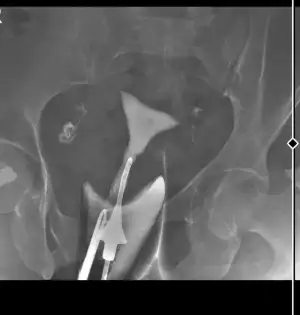

Bende bu ay Hsg çektirdim iki tüpümde de hafif tıkanıklık varmış işlem surasında ikiside açıldı şükür. Benim bir sorum olacak size. Rahim eğri duruyor sanki yoksa yatış pozisyonuyla mı alakalı, doktorum eğrilik hakkında birşey demedi, hafif tıkanıklık vardı açıldı herşey yolunda rahmin temiz dedi. Ama yinede içimde kuşku kaldı niyeyse. Anlayan bakabilir mi lütfen

Merhaba herkese😊

Oyle bisey olsaydi doktor sekil bozukluğu ile ilgili bilgi verirdi